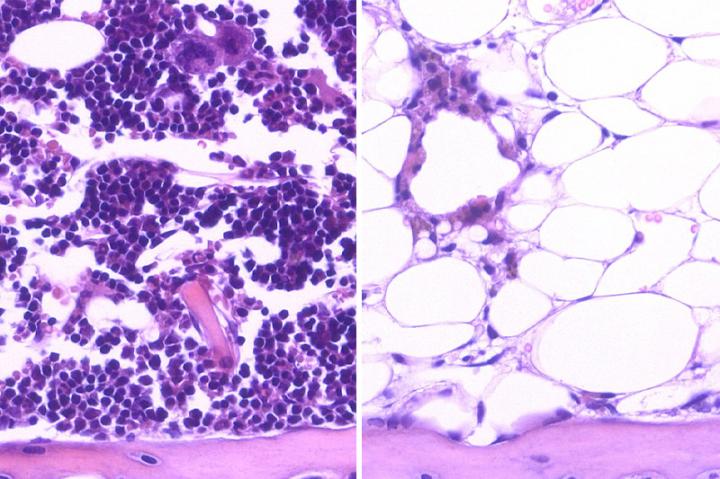

Blood-forming stem cells, or hematopoietic stem cells, are found in the bone marrow. These cells have two unique properties: They can self-renew and, through a process called differentiation, they can form any type of blood cell. A healthy immune system depends on the regenerative abilities of hematopoietic stem cells.

Common cancer therapies such as chemotherapy and radiation can eliminate cancer by killing cancer cells. But these treatments also damage hematopoietic stem cells, which can impede the cells' ability to regenerate blood, slowing the immune system and resulting in a longer, more complicated recovery for people with cancer. Previous research indicated that certain genes may alter hematopoietic stem cells' regenerative capacity by either accelerating or hindering the cells' ability to restore the immune system, but more research was needed to pinpoint the specific genetic activity and effects.